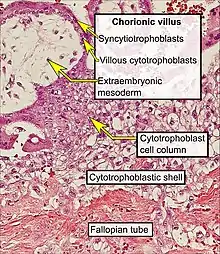

Section through embryonic area of Vespertilio murinus to show the formation of the amniotic cavity. Histopathology of a chorionic villus, in a tubal pregnancy

Histopathology of a chorionic villus, in a tubal pregnancy Histopathology of placenta with increased syncytial knotting of chorionic villi, with two knots pointed out.